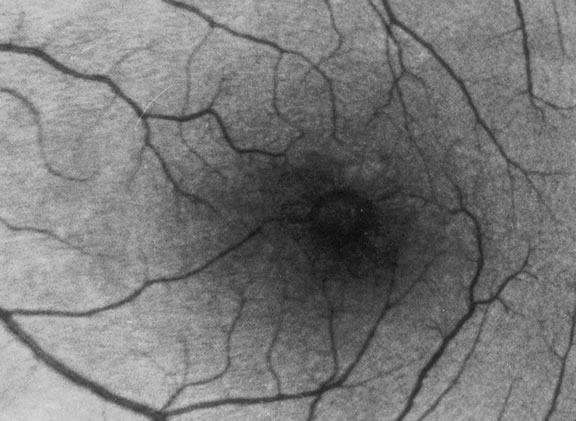

The nature of the adhesion between the vitreous cortex and the ILM is enigmatic. This adhesion is strongest at the optic nerve, the macula, the vitreous base, and retinal vessels. Foos6 demonstrated attachment plaques between Müller's cell cytoplasm and the ILM in the basal and equatorial retina (Fig. 2). Vitreous traction mediated by vitreous fibrils may contribute to these adhesions. These attachment plaques are not present posterior to the equator except where the ILM is thinned in the fovea. This anatomic variation in the fovea region may play a role in the pathogenesis of some of the vitreomacular disorders.